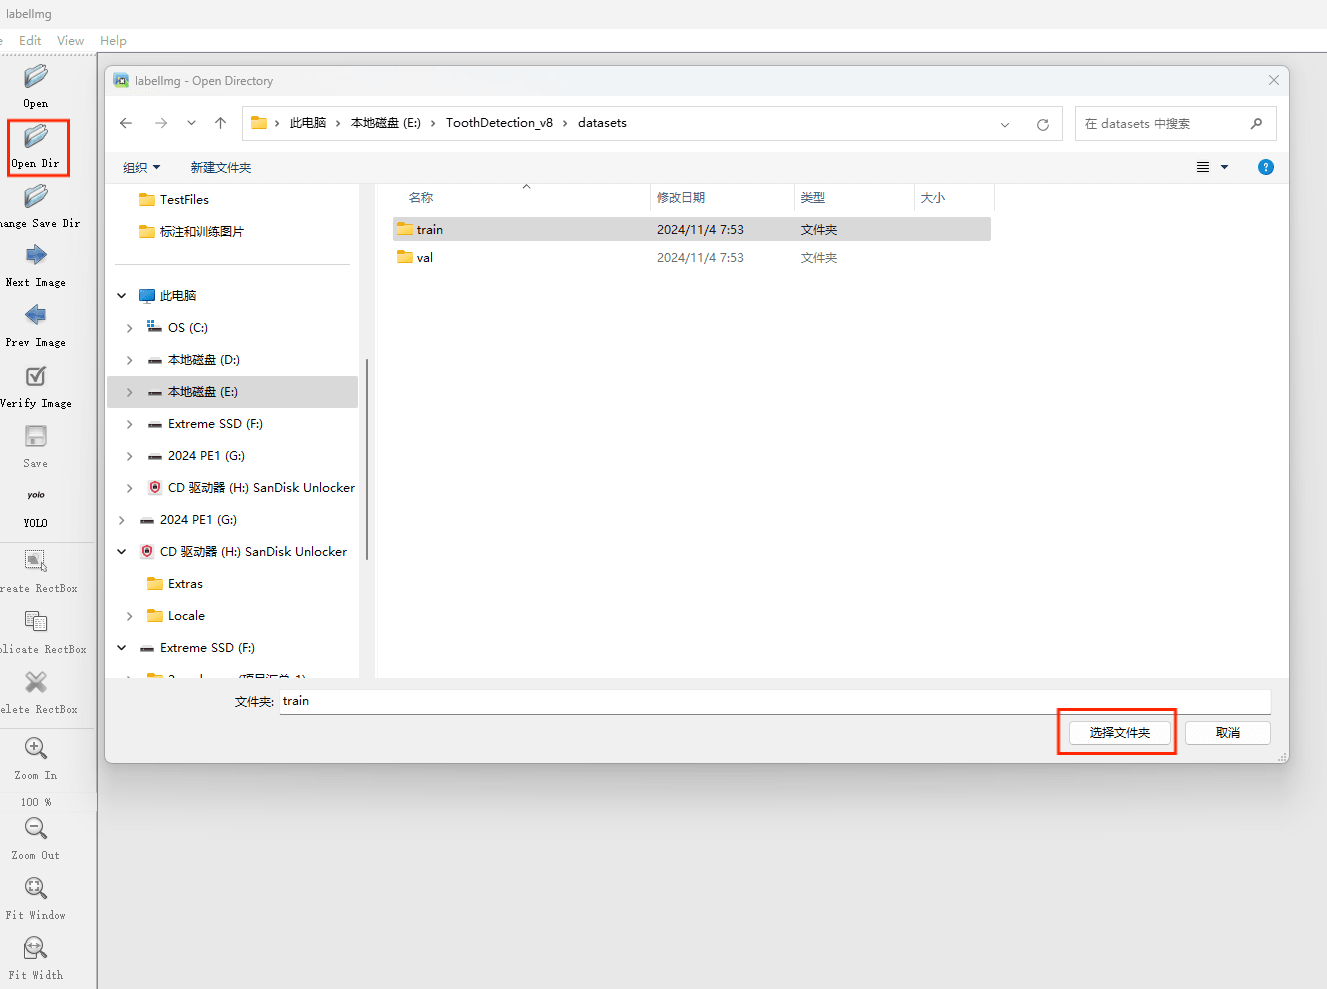

通过搜集关于数据集为各种各样的口腔牙齿CT影像相关图像,并使用Labelimg标注工具对每张图片进行标注,分6检测类别,分别是’阻生牙’,’龋齿’,’根管治疗’,’修复体’,’牙体修复’,’残根’。

目标检测标注工具

(1)labelimg:开源的图像标注工具,标签可用于分类和目标检测,它是用python写的,并使用Qt作为其图形界面,简单好用(虽然是英文版的)。其注释以 PASCAL VOC格式保存为XML文件,这是ImageNet使用的格式。此外,它还支持 COCO数据集格式。

初识labelimg

打开后,我们自己设置一下

在View中勾选Auto Save mode

接下来我们打开需要标注的图片文件夹

并设置标注文件保存的目录(上图中的Change Save Dir)

接下来就开始标注,画框,标记目标的label,然后d切换到下一张继续标注,不断重复重复。